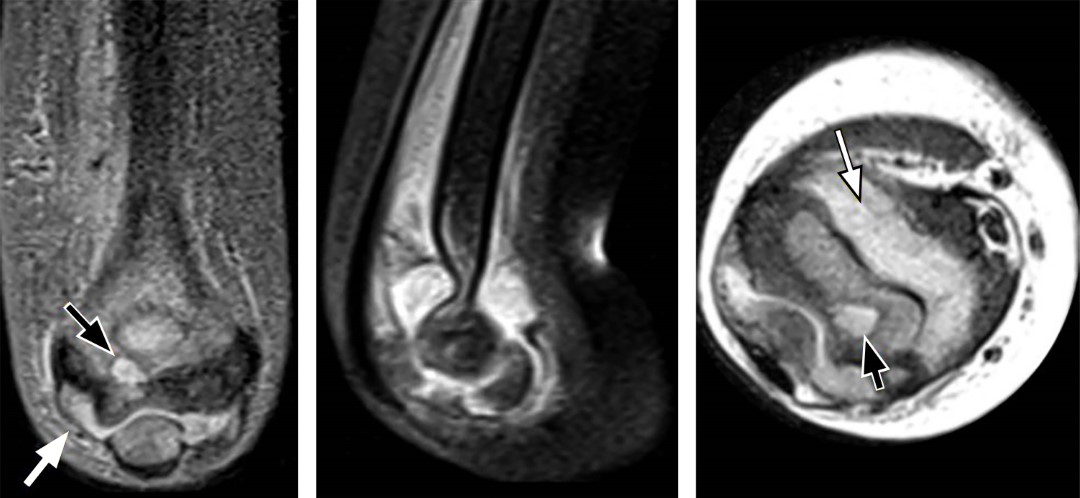

Figura 1